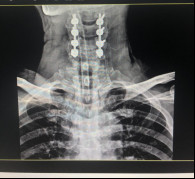

(術(shù)前拍片)

在完善了各項相關(guān)檢查后,張阿伯被診斷為:頸部脊髓損傷,不完全癱瘓及全身多處骨折,我院脊柱科主任戈才華建議其入院并接受頸后路頸椎融合手術(shù)。